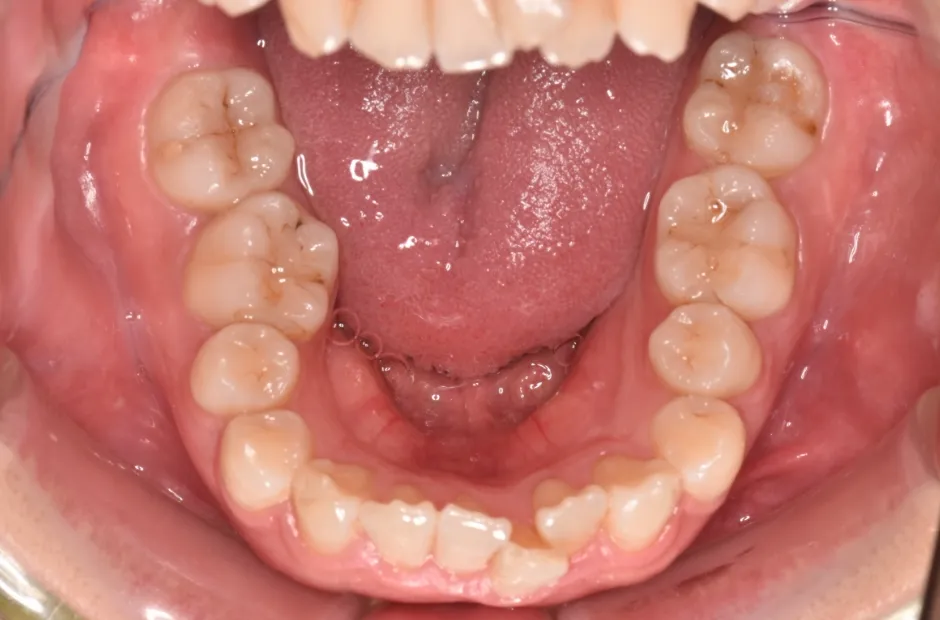

開咬

| 診断名・主訴 | 開咬 |

|---|---|

| 年齢・性別 | 18歳・男性 |

| 治療期間・回数 | 1年 12回 |

| 治療に用いた主な装置 | ロール付きリンガルアーチ |

| 抜歯部位 | なし |

| 治療費 | 70万円(税抜) |

| リスク・副作用 | 装置による違和感・疼痛・歯肉退縮・歯根吸収・虫歯のリスクなど |

治療前